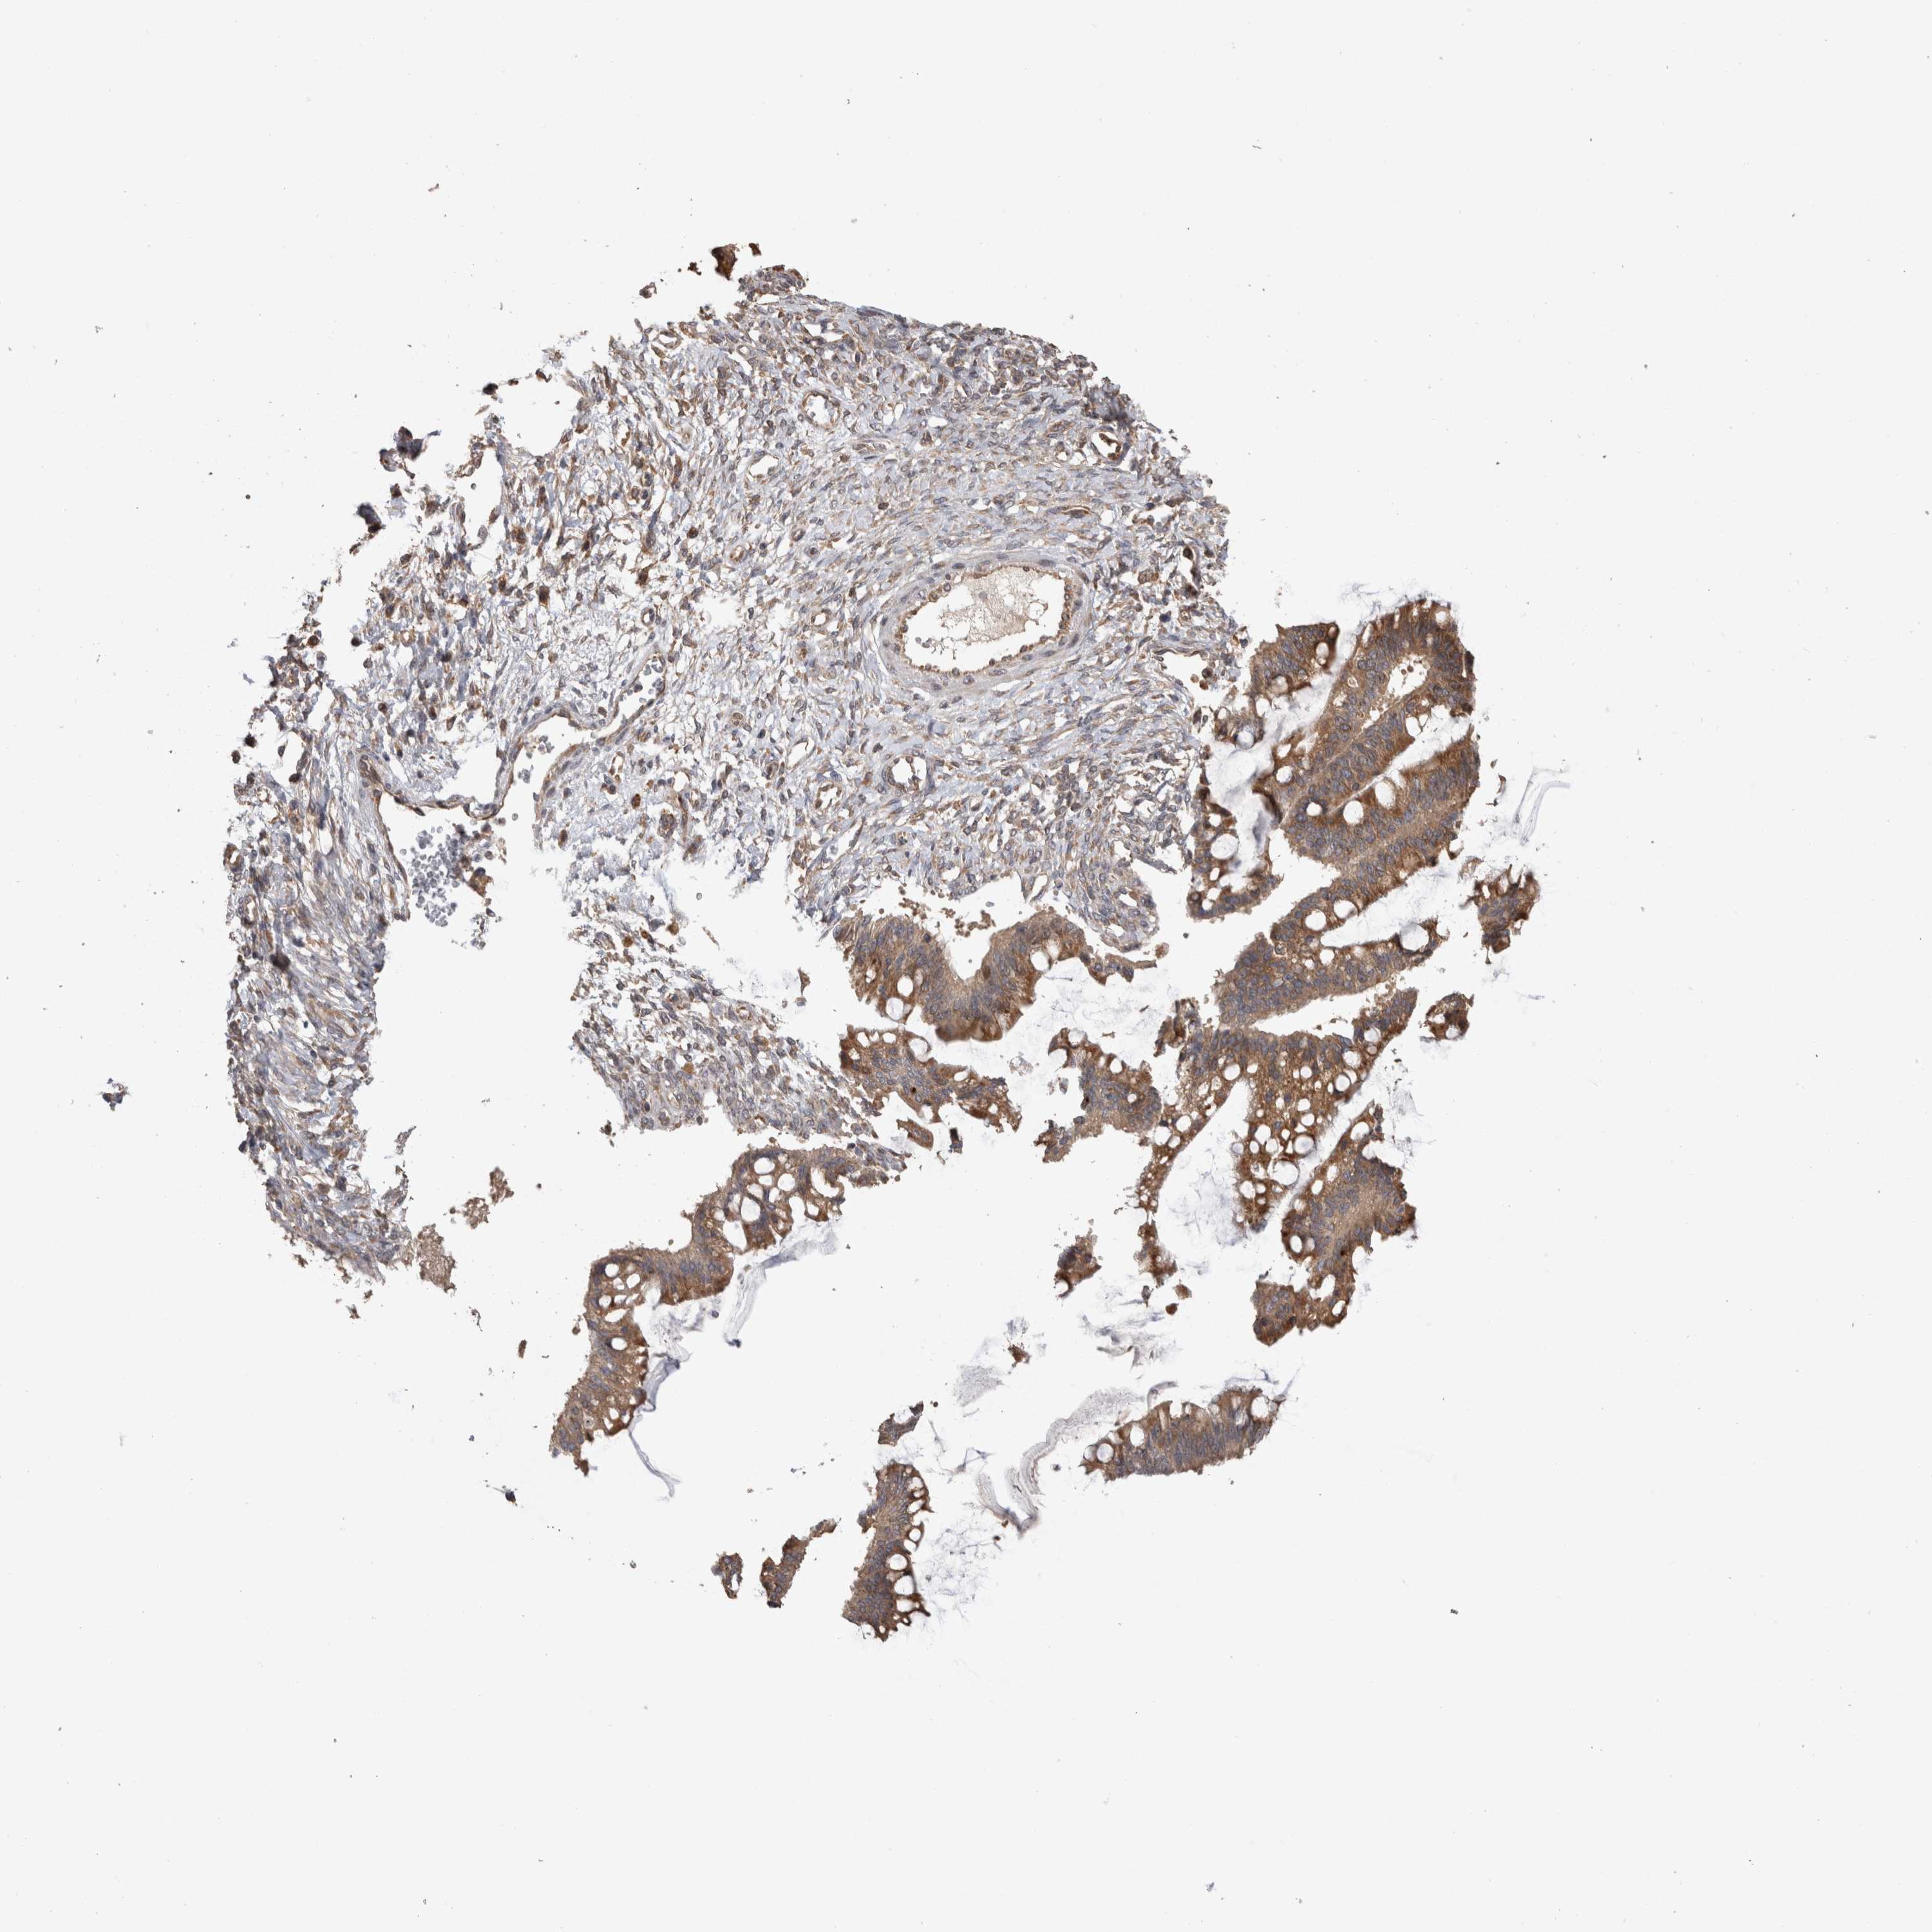

OVARIAN CANCER - Protein expressioni

A mouse-over function shows sample information and annotation data. Click on an image to view it in a full screen mode. Samples can be filtered based on level of antibody staining by selecting one or several of the following categories: high, medium, low and not detected. The assay and annotation is described here.

Note that samples used for immunohistochemistry by the Human Protein Atlas do not correspond to samples in the TCGA dataset.

Antibody stainingi

Antibody staining in the annotated cell types in the current human tissue is reported as not detected, low, medium, or high, based on conventional immunohistochemistry profiling in selected tissues. This score is based on the combination of the staining intensity and fraction of stained cells.

Each image is clickable and will lead to virtual microscopy that enables deeper exploration of all samples and also displays staining intensity scores, fraction scores and subcellular localization as well as patient and tissue information for each sample.

Antibody HPA026552

Antibody HPA026557

Staining

High

Medium

Low

Not detected

Intensity

Strong

Moderate

Weak

Negative

Quantity

>75%

75%-25%

<25%

None

Location

Nuclear

Cytoplasmic/membranous

Cytoplasmic/membranous,nuclear

Cystadenocarcinoma, serous, NOS

Carcinoma, endometroid

Cystadenocarcinoma, mucinous, NOS

Carcinoma, NOS